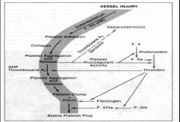

| 14:42, 19 October 2006 | Thrombosis1.jpg (file) |  |

67 KB | 1 | ||